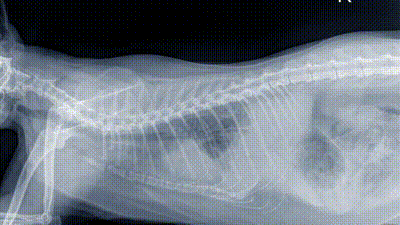

Set in Central Michigan's farm country, this reality series follows the work done at Pol Veterinary Services. Specializing in large farm animals, Dr. Pol treats horses, pigs, cows, sheep, alpacas, goats, chickens and even an occasional reindeer. The program also features Dr. Brenda Grettenberger, who has worked with Dr. Pol since 1992.